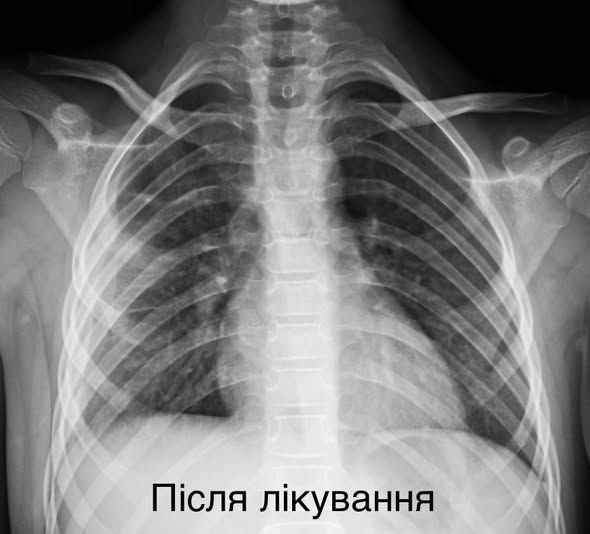

Легені маленької пацієнтки після лікування

Не пропустіть найважливіше Додайте ZAXID.NET у вибрані в GoogleМаленькій пацієнтці провели малоінвазивне втручання. Через два розрізи, розміром до 1 см, хірурги дісталися до ураженої легені, забрали гнійно-некротичні вогнища і зберегли дитині легеню.

Після операції дівчинка перебувала в реанімації на штучній вентиляції легень (ШВЛ). Нині пацієнтка вже не потребує кисню, дихає самостійно і активно відновлюється.